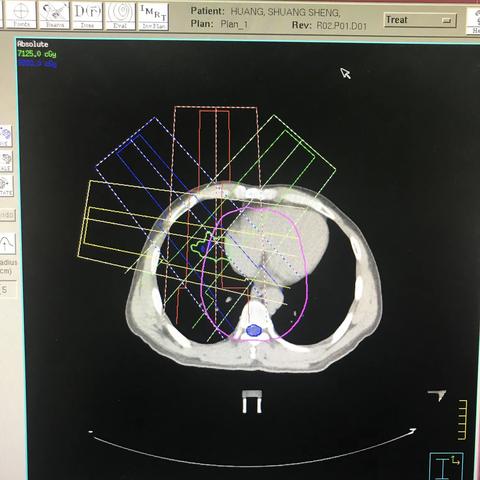

肝癌,4DCT非共面,75GY/25F,腹部压迫